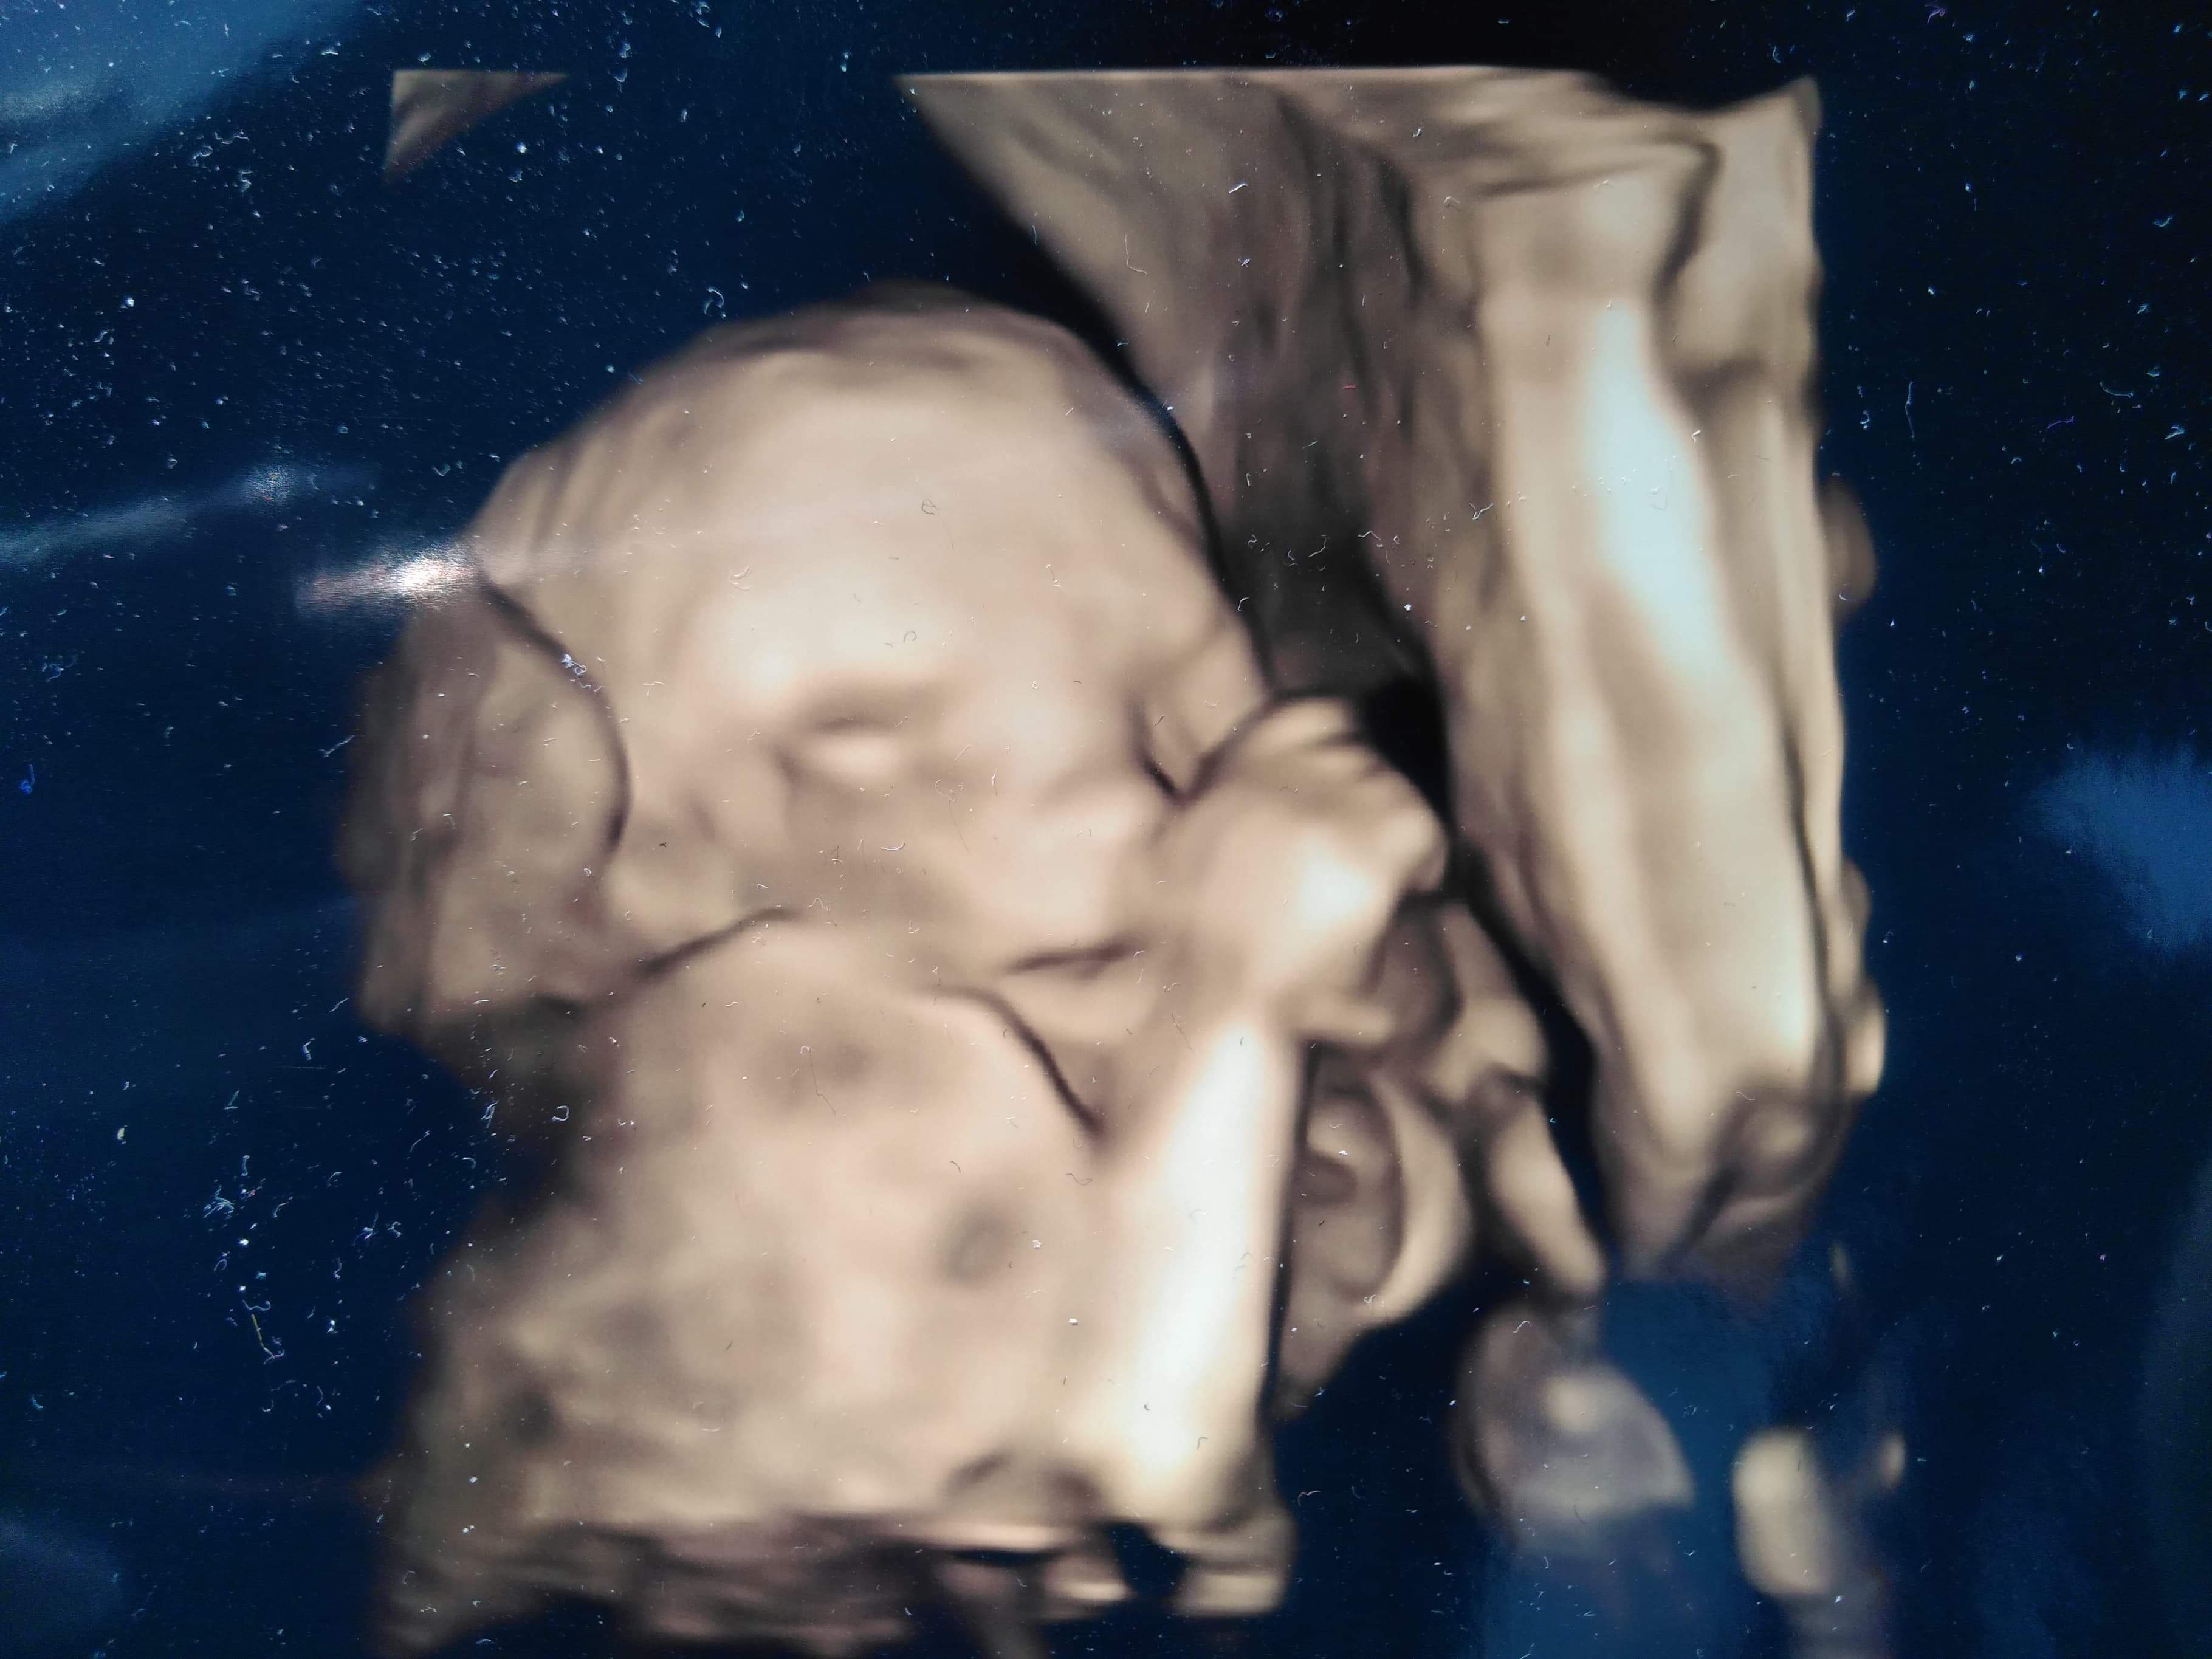

Dziewczyny skąd macie takie sztosowe zdjęcia 3D? Kto takie zrobi i ile się za to płaci? 🥰🥰🥰

moja doktor na badaniach prenatalnych robi takie zdjęcia, ale tylko jak dziecko się dobrze ułoży i je widać :) z synem mam takie dwa zdjęcia, a teraz z córką nie dostałam, bo z żadnego nie dało się takiego zrobić, była pozakrywana i brzydkie były te zdjęcia niestety...moze na połówkowych dostanę :) to mój synek w 20 tygodniu ciąży :) 😍

Załączniki

• received_601259990366604.jpeg

received_601259990366604.jpeg

356,3 KB · Wyświetleń: 96